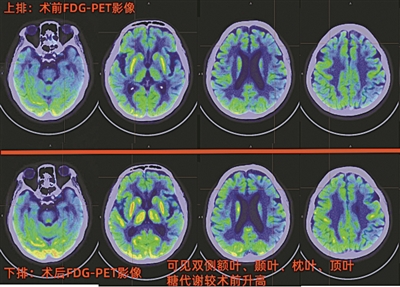

术前FDG-PET影像以及术后FDG-PET影像

术后一个半月后,阿欣母亲在医院进行了术后PET—CT复查,FDG指标的检查结果发现,其颅内多个区域的糖代谢功能较术前有明显改善。“这说明手术是有效果的,患者脑部认知功能在慢慢恢复。”北京大学深圳医院核医学科主治医师杨红杰介绍说。